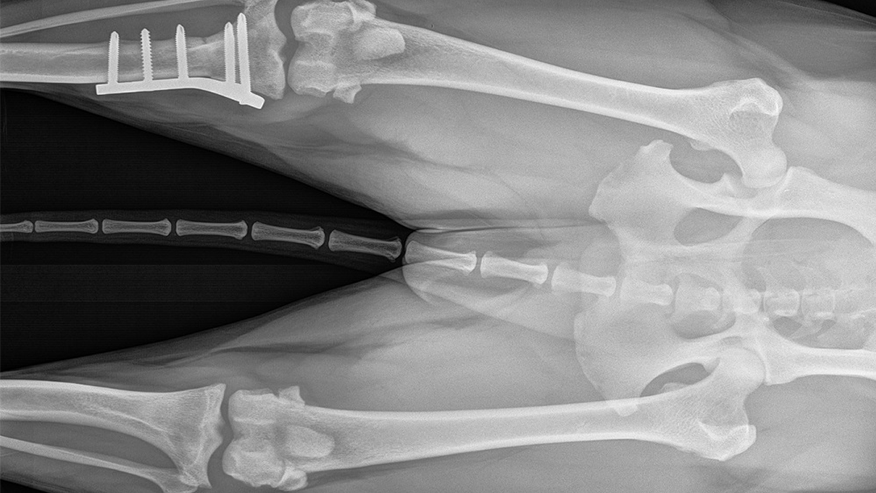

Orthopedic surgery involves surgery of the bones, joints, muscles, tendons, and ligaments. Fractured bones and torn ligaments are some of the most common injuries seen by the veterinary surgeon. In many cases.... Read more

Our hospital offers a wide range of Orthopedic Surgery services to cope with a wide range of injuries and conditions. In the case of a broken leg, for example, our surgeons can perform such procedures as bone plating, pinning and/or wiring to successfully mend the fractured bones. On the other hand, if your pet experiences a knee ligament injury, procedures such as a TPLO (Tibial Plateau Leveling Osteotomy) or extracapsular repair may be recommended.... Read more